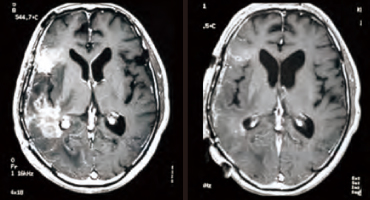

上記以外の脳腫瘍では、X線治療に抵抗性の悪性髄膜腫でも縮退を得、その効果には

括目すべきものがあります(図:大阪医科大学症例)。